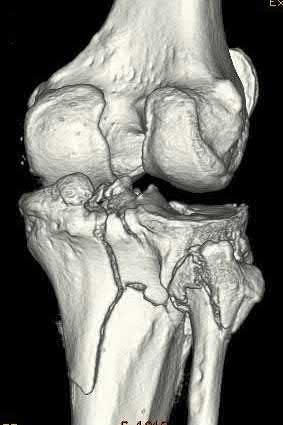

A 27-year-old male is involved in a motor vehicle collision and presents to the ER with the right lower extremity injury shown in Figures A and B. He undergoes immediate closed reduction and the post-reduction CT is shown in Figures C and D. The patient undergoes percutaneous surgical screw fixation of the injury. At 2 years followup, he presents with a supination deformity with decreased eversion of the foot at rest. Radiographs reveal no evidence of talus subchondral sclerosis or collapse. Which of the following is the most likely cause of the finding in this patient?

The patient has sustained a displaced talar neck fracture with medial comminution which requires open reduction and internal fixation to restore anatomic alignment. The patient has likely sustained varus malunion which is a common deformity noted with non-anatomical reduction leading to hindfoot supination and decreased eversion.

Talar neck fractures, while uncommon, can lead to significant morbidity in the ambulatory patient. Treatment of these injuries requires prompt reduction due to the tenuous blood supply to the talus. The most common complications noted after a talar neck fracture are avascular necrosis, subtalar arthritis, tibiotalar arthritis, and varus malunion. A talus varus malunion generally occurs due to medial talar neck comminution and/or non-anatomic reduction of the injury. This deformity can lead to decreased eversion and a supination deformity causing patients to ambulate on the lateral aspect of the foot. These malunions are generally treated with a medial opening wedge osteotomy.

Figures A and B are the Lateral and AP radiographs of a displaced talar neck fracture with tibiotalar dislocation. Figures C and D are the post-reduction sagittal foot CT cuts that reveal a displaced talar neck fracture with medial

comminution.